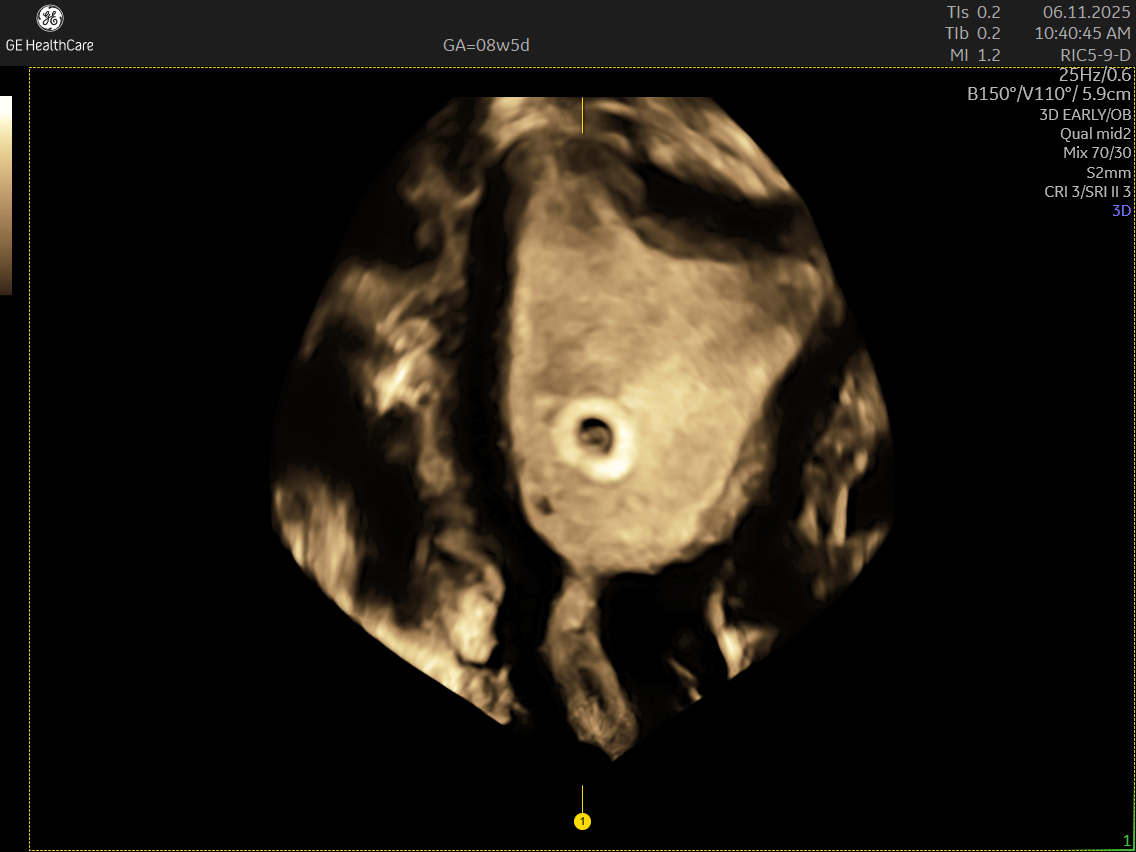

A Dating and Viability Scan is the first critical ultrasound in your pregnancy journey. Performed between 6 – 8 weeks, it confirms your pregnancy’s health, establishes how far along you are, and ensures an accurate start to your prenatal care.

- Usually conducted transvaginally for clear imaging

What Can The Scan Detect?

- Latest ultrasound technology for precise imaging